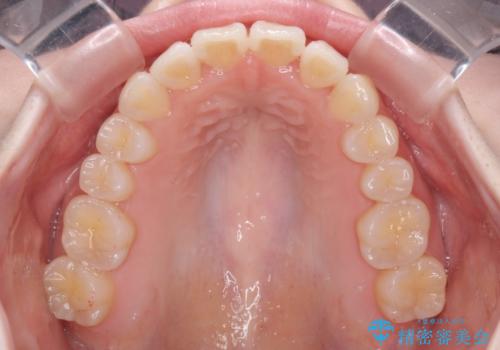

- 前歯の捻れと、ちょっとした出っ張りを気にして来院された患者様です。

歯と歯の間を削る(IPR)ことでデコボコを解消し、インビザラインで整えることとしました。

インビザライン治療特有の奥歯が接触しない時期が続き、当初予定よりも期間がかかりましたが、最終的には安定した咬み合わせと、整った前歯になりました。